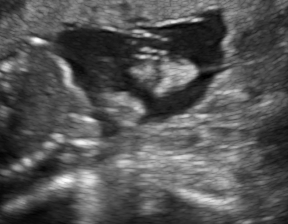

We demonstrate the practical applicability of our method on a challenging medical application, the classification of standardized fetal ultrasound (US) views during prenatal screening. In many countries, US imaging is clinical routine for prenatal health care. The classification of standardized views is important for a consistent, cross-institutional identification of possible abnormalities [47]. Early detection of pathological development can inform following treatment and delivery options [55, 25]. DNNs have shown promising performance to support this task [2]. However, ultrasound images are often hard to interpreted [40]. Anatomical structures have inconsistent appearance [2] and contain different orientations and shapes of anatomical landmarks [1]. Labeled training data is often insufficient as annotating medical images requires significant expertise and is prohibitively expensive in both time and labor. Manifestation of acoustic shadows [17, 44] as shown in Fig. 2(a) as well as different imaging devices as shown in Fig. 2(b) can lead to a domain shift problem for vanilla DNN classifiers. Exploring domain adaptation in fetal US enables DNN classifiers to be effectively utilized on a wider range, which supports identification of abnormalities from varying data sources. This can benefit prenatal healthcare.

We evaluate the proposed method on two fetal US standard plane classification tasks, where the domain shifts are respectively caused by shadow artifacts (Fig. 2(a)) and different image acquisition devices (Fig. 2(b)). For both tasks, images from source and target domains are unpaired and collected independently. We show the key results in the main paper and detailed implementation, network architectures as well as more results in the supplemental Appendix.

The fetal US dataset consists of 2D fetal US images sampled from 2694 2D US examinations with gestational ages between weeks (iFIND Project 555http://www.ifindproject.com/ ). Eight different US systems of identical make and model (GE Voluson E8) were used for the acquisitions to eliminate as many unknown image acquisition parameters as possible. Six different anatomical standard plane locations have been selected by an experienced sonographer, including Four Chamber View (4CH), Abdominal, Femur, Lips, Left Ventricular Outflow Tract (LVOT) and Right Ventricular Outflow Tract (RVOT). The images have additionally been classified by an expert observer as shadow-containing or shadow-free. In this experiment, the source domain contains shadow-free images (see Fig. 2 (b) SF) while the target domain has shadow-containing images from less favorable imaging conditions (see Fig. 2 (b) SC). Training data consists of all six standard planes from the source domain as well as Abdominal, LVOT and RVOT from the target domain. We aim to separate anatomical features (categorical features) and shadow artifacts features (domain features) to obtain generalized anatomical features for achieving high performance of standard plane classification on (4CH, Femur and Lips from target domain). Here, contains 4CH, Abdominal, Femur, Lips, LVOT and RVOT from the source domain and contains Abdominal, LVOT and RVOT from the target domain. Hyper-parameters to in Eq. 11 are for the proposed MIDNet model and is additionally for MIDNet+.